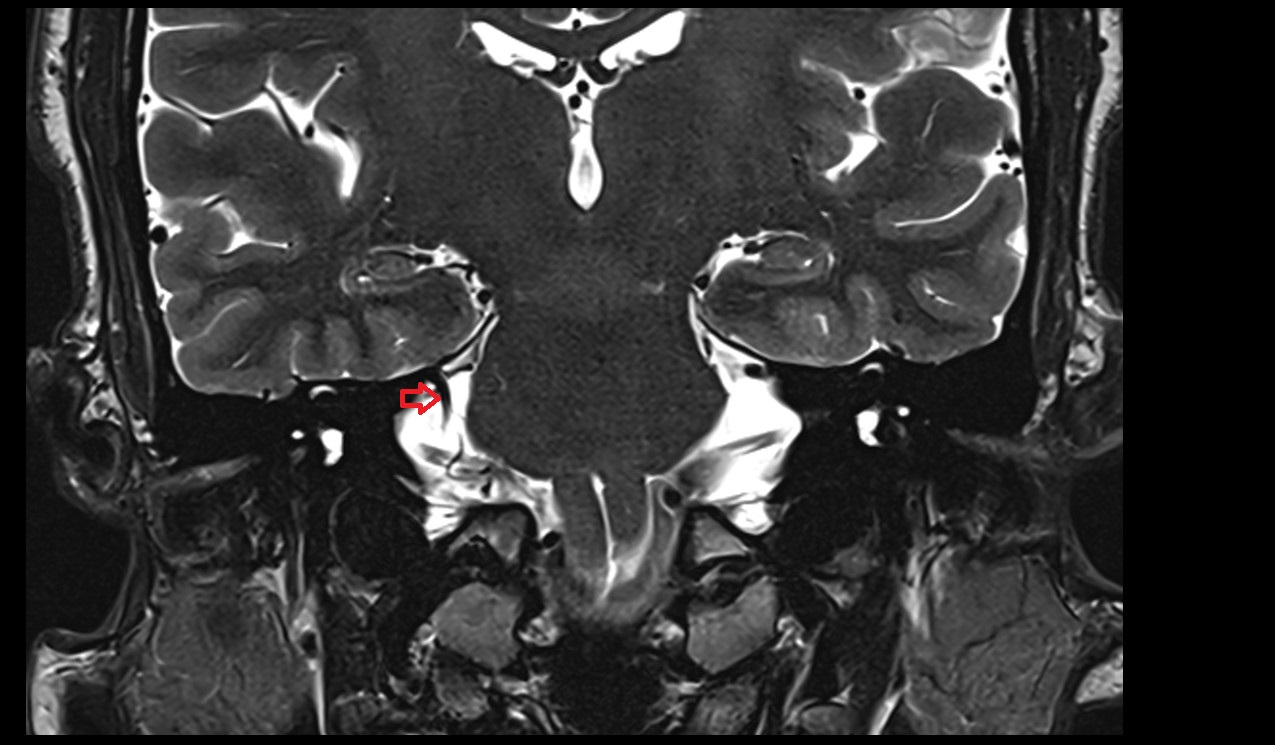

- Cerebellum